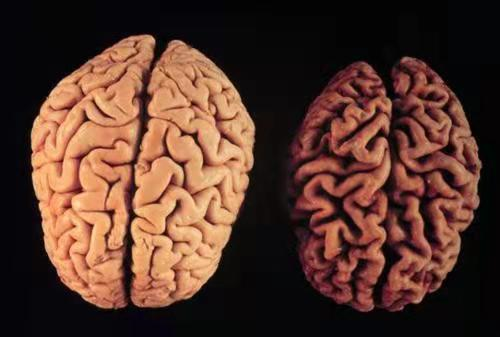

老年痴呆的大脑和正常人的到底有什么区别呢?怎么就变痴呆了呢?

在我科治疗一周后可独立步行.左侧是他萎缩的小脑,右侧是正常人小脑.